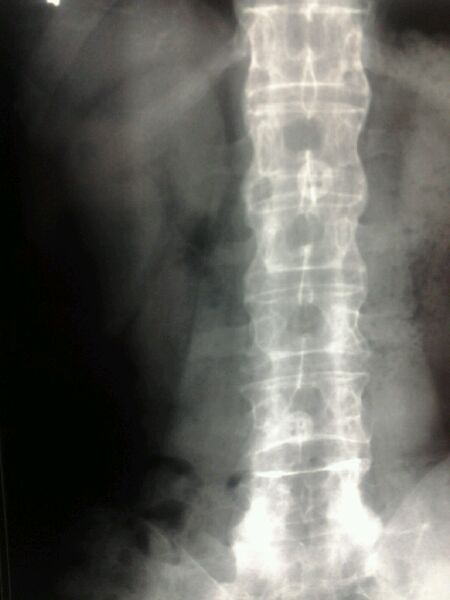

附上前年拍的,脊椎竹节状,已经是晚期了

2015年08月08日 09点08分 13